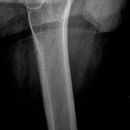

Becken a.p.

>90% aller Beckenringfrakturen lassen sich in der Übersichtsaufnahme, ggf. mit zusätzlicher Inlet und Outlet- Aufnahme (Bestimmung von Richtung und Ausmaß der Dislokation), diagnostizieren;

Cave:

- Bei V.a. Frakturen von Os sacrum und Azetabulum, sowie im Bereich der ISG -> CT-Indikation!!

- Zusätzliche Organläsionen und retroperitoneale Massenblutungen!

Beurteilungskriterien

- Symmetrie des Beckenskeletts, Position der Darmbeinkämme

- Weite und Symmetrie von Symphysenspalt (< 6mm) und ISF (< 4mm)

- Querfortsätze der unteren LWS, Kontur der Sakralforamina, ggf. CT

- Kontinuität der ilioischiadischen und iliopubischen Linie

- Azetabulumfraktur: vorderer und hinterer Pfannenrand, Pfannendachkontur, Köhlersche Tränenfigur, ggf. Zusatzaufnahmen (ap-Zielaufnahme, axiale, Ala- und Obturatoraufnahme), sowie CT

- Schenkelhalswinkel, Weite des Hüftgelenksspalt (4-5mm nach medial, 3-4mm nach kranial)

- Hüftluxation? Hüftkopf in der Beckenübersicht und in der axialen Aufnahme in der Pfanne zentriert?